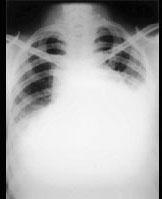

问题 35岁男性患者,一个月前开始间歇性发热,咳嗽、咳痰,足部肿胀,伴颈静脉怒张,行X线、CT检查如图所示,请选择正确的答案 ( )

选项 A、考虑原发性心包间皮瘤 B、考虑为心包炎 C、CT示示心包内见软组织肿块影 D、CT示心包弥漫性增厚,未见钙化影 E、X线示心影增大

答案 ACDE